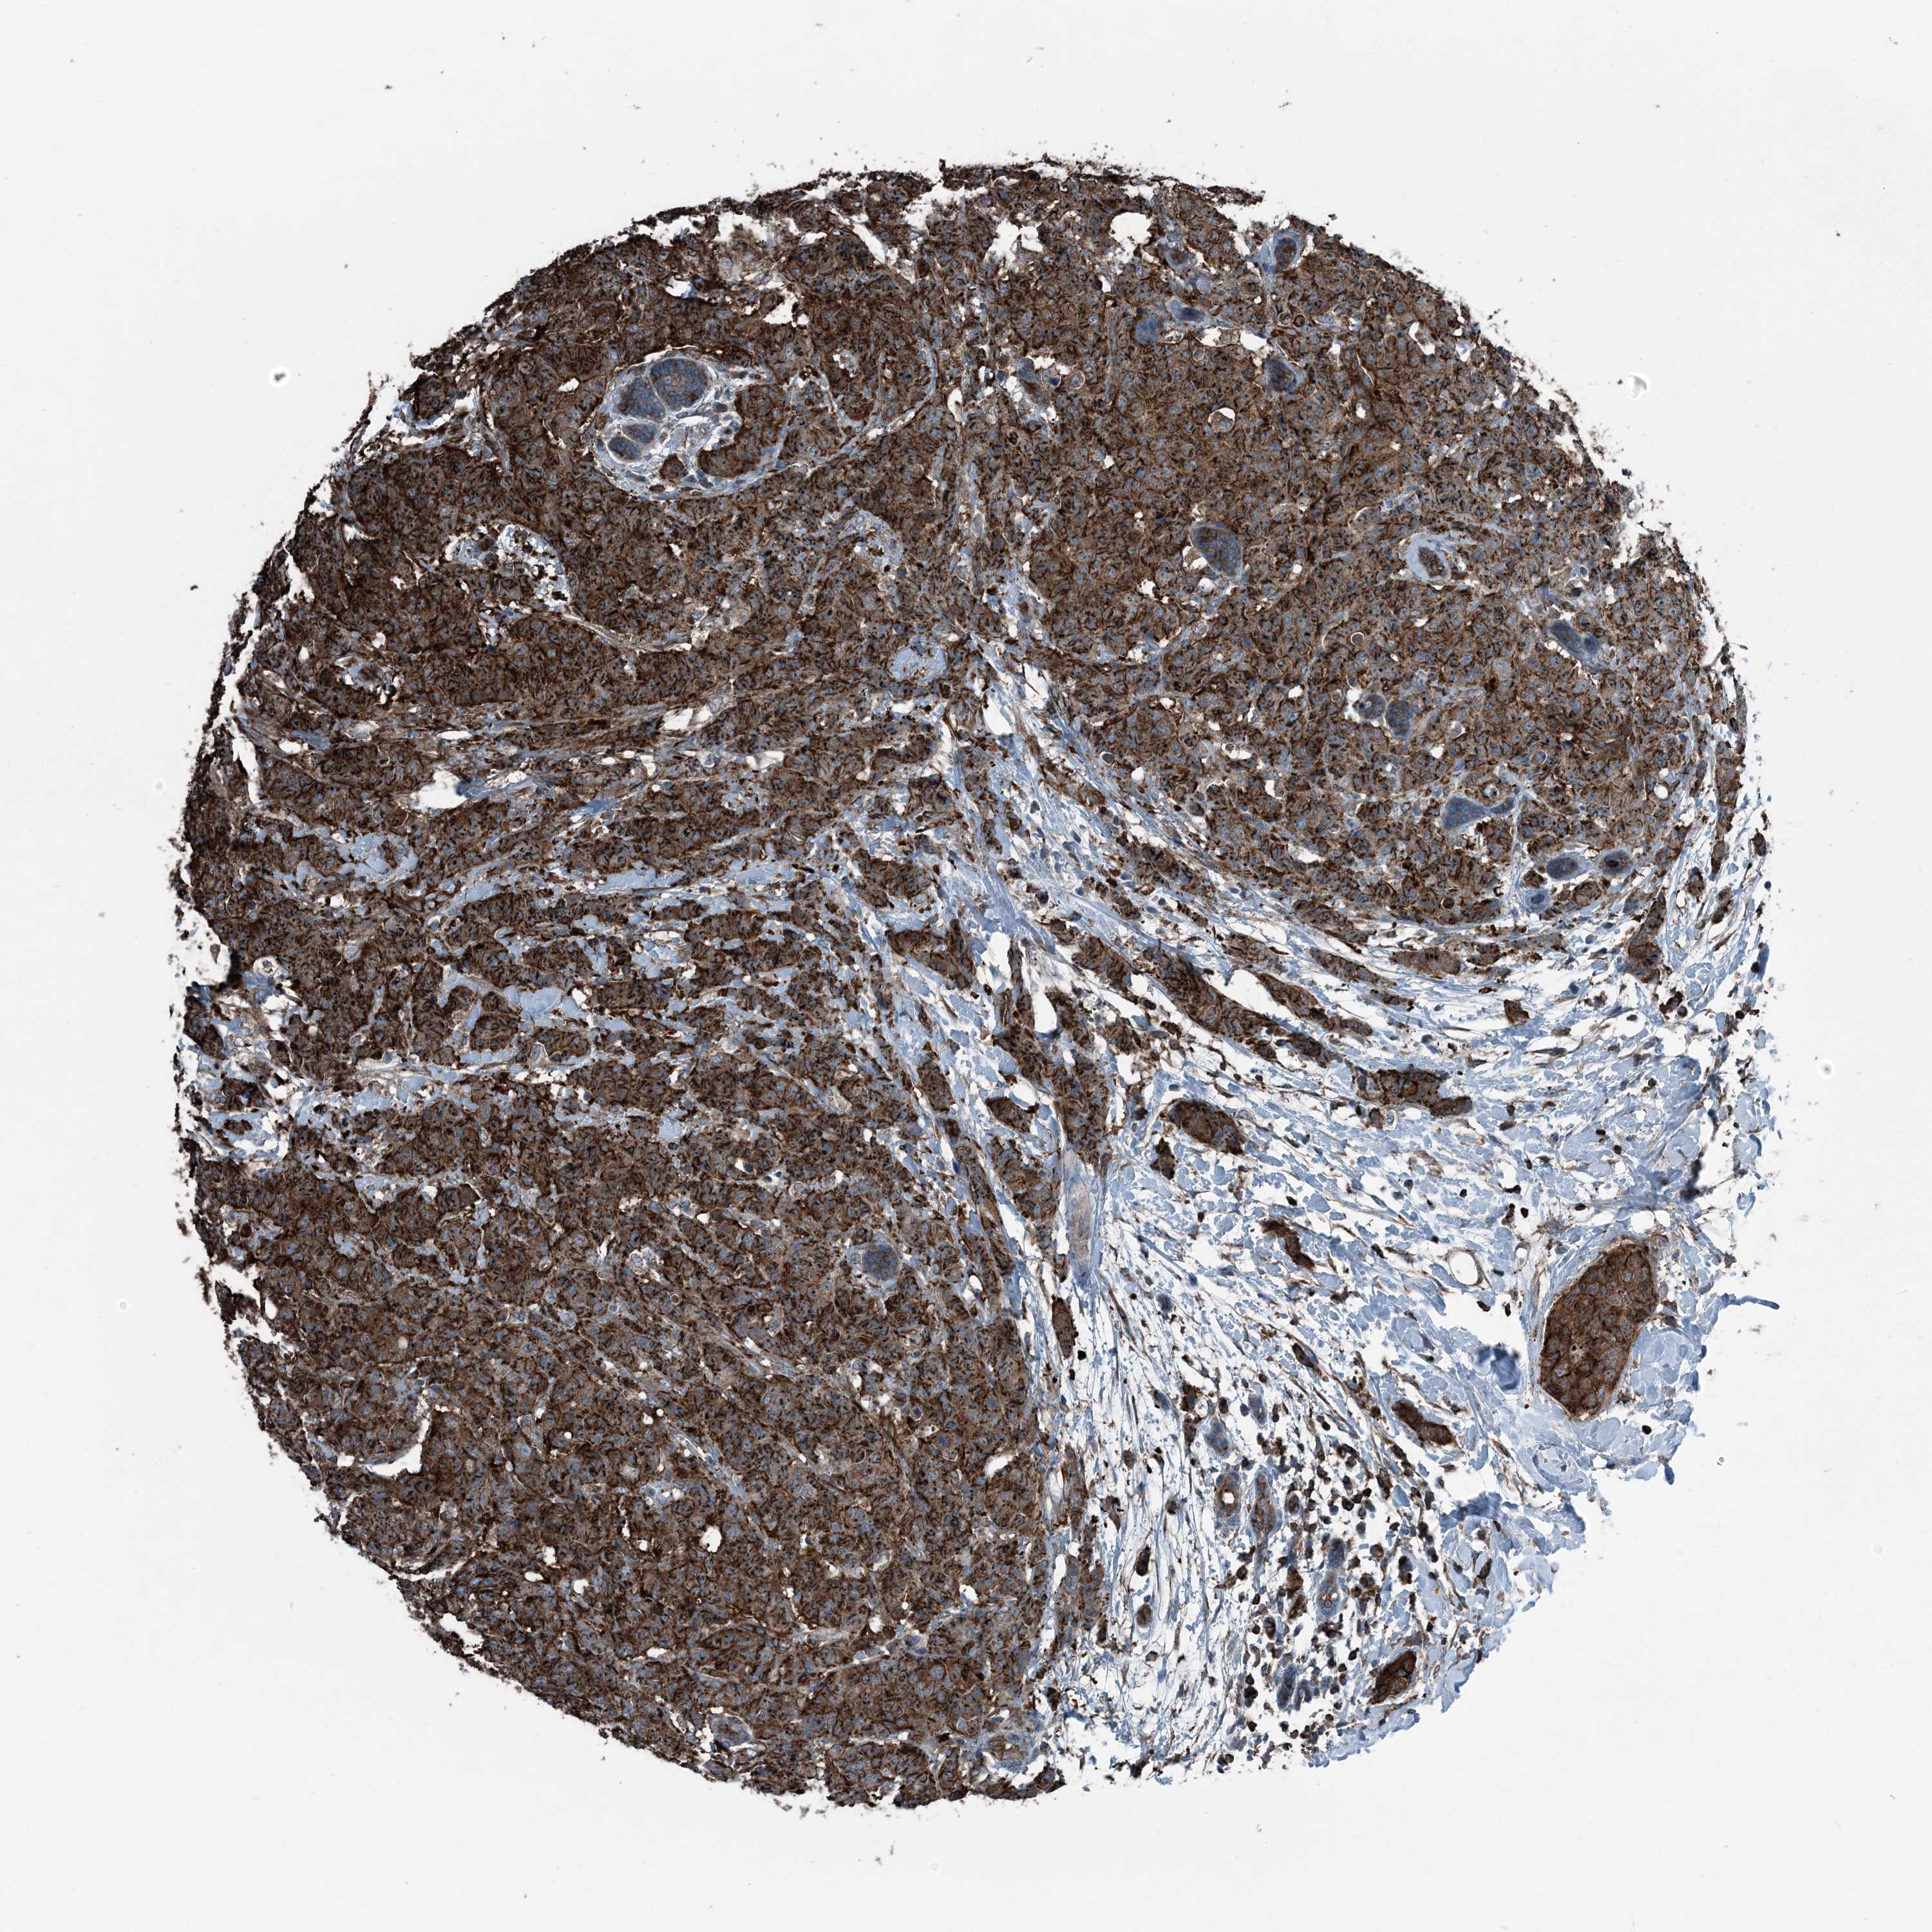

BRCA TCGA BRCA VALIDATION PROTEIN EXPRESSION

ANTIBODIES

AND

VALIDATION